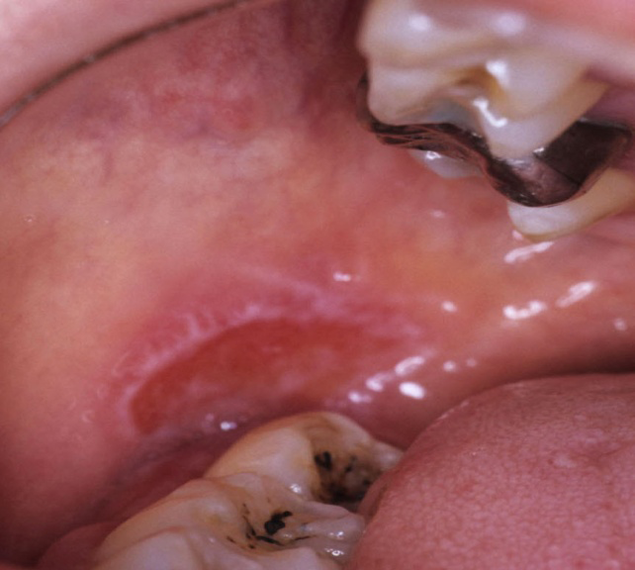

口腔扁平苔癬(水疱型)

歯槽部に近接した頬粘膜に生じた水疱型扁平苔癬